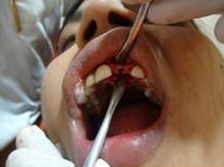

Punch Cut

Placement of Bone Grafting

After Punch Cut

Drilling for Implant

Bone Graft in Extraction Socket

Use of Bone Graft & GTR membrane for an Implant

Suturing after Bone Grafting

Drilling Implant Socket

Suturing after Implant Placement